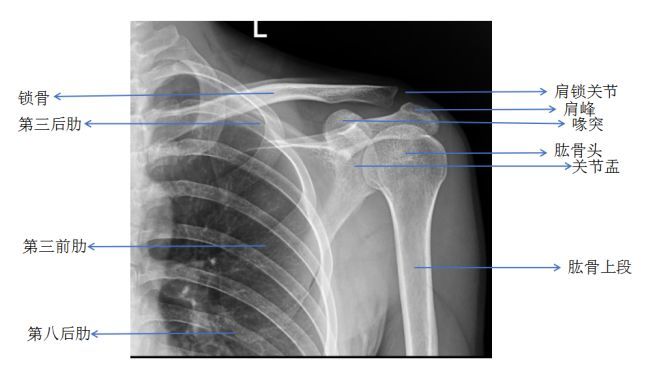

正常肩关节

正常肩关节,

肩关节脱位不重要?来看看专家怎么说.

人体肩关节解剖示意图人体解剖图